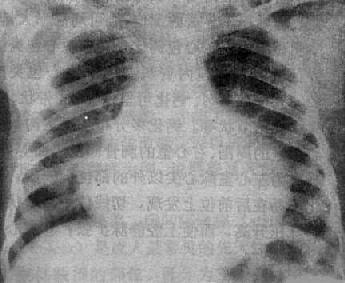

图3-2-18 心包积液(后前位)

心影向两侧普遍增大,心缘正常弧度消失,

上腔静脉增宽,主动脉影缩短,肺纹理减少

X线表现 (图3-2-18),不论积液的性质和病原如何,都可以显示其共同特点:①心包积液在300ml以下者,心影大小和形状可无明显改变,X线难以发现。中等量积液,液体从心包囊最下部分向心两侧扩展,后前位可见心影向两侧普遍增大,心缘正常弧度消失,心形状呈烧瓶状,如积液缓慢增多,则呈球形;②心包积液可使体静脉血液回流至右心房受阻,致使上腔静脉增宽;③由于心包在心底部的附着处高于心与大血管的交界下,增大的心影可以超过心、大血管交界处,增大的心影可以超过心、大血管交界以上,故使主动脉影缩短;④心缘搏动减弱或消失,而主动脉搏动则表现正常;⑤体静脉血液回流到右心房受阻,右心室排血量减少,因而肺纹理减少或不显。如合并左心衰竭,则有肺瘀血现象。